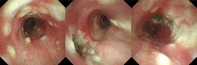

气管支气管结核是一种在治疗慢性咳嗽患者时需要特别注意的疾病,例如支气管哮喘患者。

Tracheobronchial tuberculosis is a disease that requires careful attention when treating patients with chronic cough, such as those with bronchial asthma.